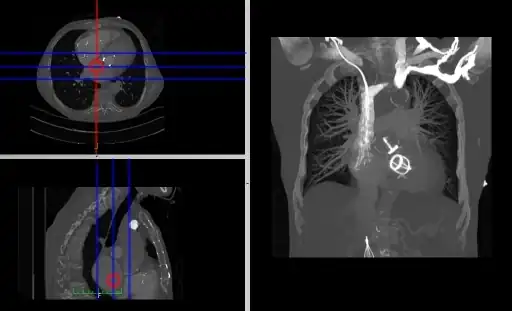

Coronal and sagittal reconstructions are referred to as Orthogonal MPRs because the perspectives generated are from planes of image data which are at right angles to each other. Composite MPR displays can be generated so that linked cursors or crosshairs can be used to locate a point of interest from all three perspectives, as illustrated in these images:

A composite orthogonal MPR display with linked cursors on the axial and sagittal images.

A composite orthogonal MPR display with linked crosshairs on all three images.

This form of image presentation is sometimes referred to as a TCS display – implying the viewing of Transaxial, Coronal and Sagittal slices. It can be combined with the slice projection methods we discussed earlier, as illustrated in the two sets of images below, where the blue lines highlight the limits of the coronal projections:

Axial and sagittal reconstructions from the SPECT lung-perfusion study with various coronal projections.

Axial and sagittal reconstructions from the CT study with a coronal MIP.